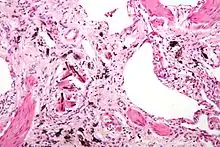

Extensive fibrosis of pleura and lung parenchyma

The arrow points to an uncoated segment of asbestos fiber in this ferruginous body.

Severe pleural fibrosis with focal calcification

The black arrows point to ferrugionous bodies that are located at the periphery of a focus of non-small cell lung carcinoma, NOS.